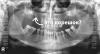

vvfslava Опубликовано 5 февраля, 2011 Поделиться Опубликовано 5 февраля, 2011 Удалили три зуба, рекомендуют удалить 6,7 снизу слева и справа предлагают ставить съемный протез. Имплантанты говорят нельзя.Неужели все так печально? Ссылка на комментарий

Doc Опубликовано 5 февраля, 2011 Поделиться Опубликовано 5 февраля, 2011 Еще как можно. И не забудьте убрать корешок справа вверху. Ссылка на комментарий

pawa Опубликовано 17 февраля, 2011 Поделиться Опубликовано 17 февраля, 2011 Простите мою серость, но что это за круглишки в области н/резцов не орто? Ссылка на комментарий

Bier Опубликовано 17 февраля, 2011 Поделиться Опубликовано 17 февраля, 2011 Простите мою серость, но что это за круглишки в области н/резцов на орто? калибровочные шарики. Ссылка на комментарий

Doc Опубликовано 17 февраля, 2011 Поделиться Опубликовано 17 февраля, 2011 Простите мою серость, но что это за круглишки в области н/резцов не орто? Диаметр данных кругляшков предварительно задан. Основываясь на пропорциях программа может просчитать с достаточной точностью расстояния на ортопантомограмме. Ссылка на комментарий

vvfslava Опубликовано 18 февраля, 2011 Автор Поделиться Опубликовано 18 февраля, 2011 Простите мою серость, но что это за круглишки в области н/резцов не орто?В самом первом сообщении " удалили три зуба" .Снимок перед удалением. Я пометил которые удалили. Может зеркально не могу понять, как считаются зубы. Ссылка на комментарий

Bier Опубликовано 18 февраля, 2011 Поделиться Опубликовано 18 февраля, 2011 мдаааа а мы то тут думали... а это ваши художества оказались Ссылка на комментарий

vvfslava Опубликовано 18 февраля, 2011 Автор Поделиться Опубликовано 18 февраля, 2011 (изменено) мдаааа а мы то тут думали... а это ваши художества оказались В мыслях не было ввести в заблуждения. Думал все понятно три зуба, как указать которые,цифровой кодировкой не владею - фотошоп три точки думал все понятно. p.s. Уже сегодня, пойду удалять корешок справа вверху, опасаться сложностей?К стати справа вверху или слева . По ощущениям для меня слева верхний пятый . Изменено 18 февраля, 2011 пользователем vvfslava Ссылка на комментарий

Bier Опубликовано 18 февраля, 2011 Поделиться Опубликовано 18 февраля, 2011 снимок зеркалит, у вас слева, на снимке справа, все правильно. Ссылка на комментарий

vvfslava Опубликовано 18 февраля, 2011 Автор Поделиться Опубликовано 18 февраля, 2011 снимок зеркалит, у вас слева, на снимке справа, все правильно. Так я совсем запутался.В свое время (лет 5 назад) при лечении верхней левой пятерки, мне предлагали удалить остатки зуба от верхней левой шестерки (зуб был удален лет 25 назад). Я отказался.Я и думал что разговор идет об этом, а сейчас оказывается что и с другой стороны проблема. Ссылка на комментарий

Bier Опубликовано 18 февраля, 2011 Поделиться Опубликовано 18 февраля, 2011 ну судя по снимку, да, проблема справа, слева я не вижу остатков корней. Ссылка на комментарий